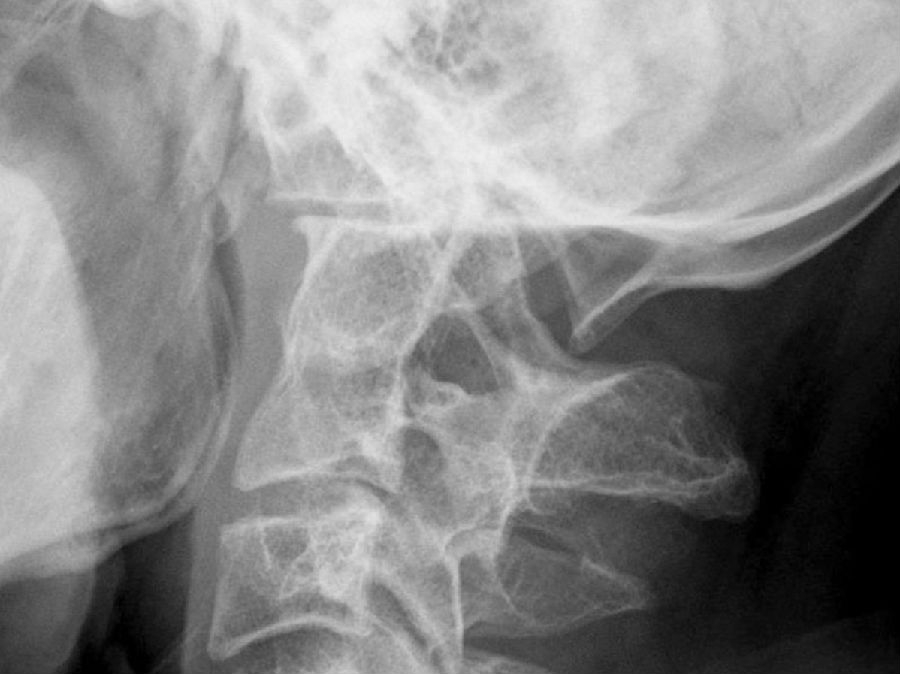

无移位后弓骨折在平片上难以诊断,特别是患者伤势严重而摄片体位受限时,更不易显示(图9)。

椎前软组织阴影增厚为骨折的间接征象。当颈3椎体前方和颈4椎体上缘前方软组织厚度超过5~7mm,颈6和颈7椎前软组织厚度超过20~22mm时,提示有骨折可能(图9)。前纵韧带前方的椎前脂肪条带影移位为骨折的另一间接征象。